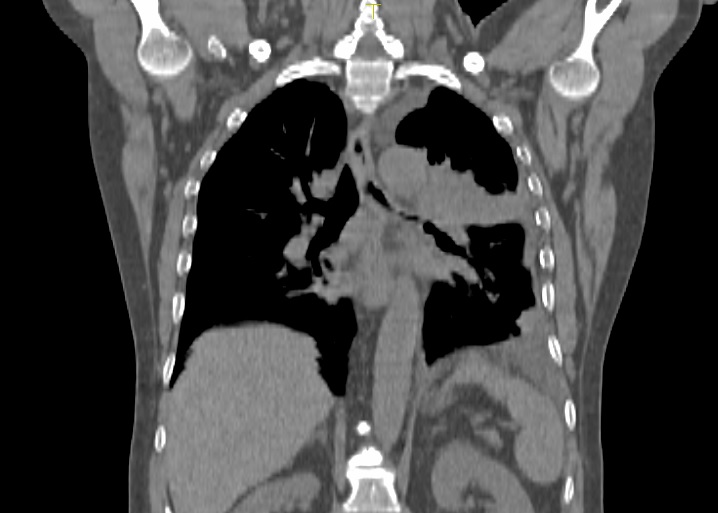

Pacientul M.L. in varsta de 56 ani, fumator de 40 ani, 20PA, s-a prezentat in clinica noastra pe data de 30.11.2022, cu diagnosticul de adenocarcinom pulmonar (neoplasm pulmonar) la nivelul lobului pulmonar superior stang, o tumora in stadiul IIIC, de dimensiuni mari T3, cu invazie ganglionara si mediastinala. Cazul a fost prezentat in Comisia Oncologica Multidisciplinara a clinicii noastre, unde s-a decis initierea tratamentului oncologic. Tumora fiind avansata loco-regional, era exclusa interventia chirurgicala in acest stadiu de boala (cancer pulmonar inoperabil).

Astfel, in perioada 5.12.2022 – 26.01.2023, pacientul a efectuat radioterapie externa cu fotoni, tehnica VMAT-CBCT, pana la doza totala DT = 66 GY/volum tinta formatiune tumorala pulmonara, un numar total de 33 fractii, concomitent cu administrarea saptamanala de polichimioterapie de radiosensibilizare, cu toleranta foarte buna.

Prezentam acest caz la scurt timp dupa finalizarea tratamentului (tratament cancer pulmonar), deoarece acesta este un caz fericit, la care s-a observat un raspuns aproape total chiar din timpul tratamentului RT, imaginile CBCT efectuate la inceputul, in timpul si la finalul tratamentului RT, pe care le atasam, aratand clar un raspuns extraordinar de bun la tratamentul efectuat.